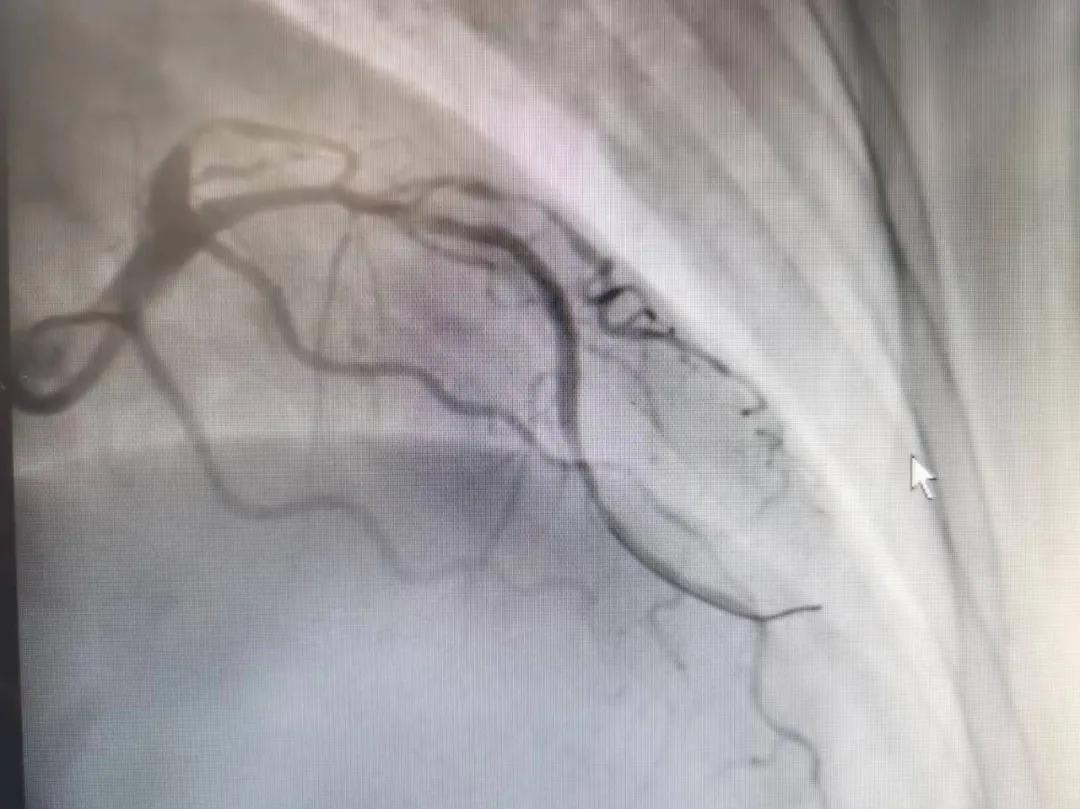

病人是位六十多歲的女性患者,有長(zhǎng)期高血壓病史,1個(gè)月前開始出現(xiàn)胸悶胸痛,口服藥物治療效果不佳,經(jīng)朋友介紹,來到市二院心血管內(nèi)科。入院后完善冠狀動(dòng)脈造影提示:前降支全程彌漫性狹窄伴鈣化,最重95%,回旋支狹窄約85%,右冠脈全程狹窄伴鈣化,最重60%。血管內(nèi)超聲顯示右冠脈開口面積3.36mm²,可見環(huán)形鈣化,考慮患者病變程度重、鈣化明顯,常規(guī)器械無法實(shí)現(xiàn)病變的良好預(yù)處理,且有很高的冠脈穿孔、血管夾層的風(fēng)險(xiǎn)。

術(shù)前

王瑾院長(zhǎng)和李慧新主任帶領(lǐng)介入團(tuán)隊(duì)充分評(píng)估,決定行前降支冠狀動(dòng)脈鈣化病變旋磨術(shù),術(shù)中應(yīng)用1.5mm旋磨頭,以15萬-17萬轉(zhuǎn)/分速度共對(duì)病變旋磨3次,累計(jì)旋磨時(shí)間60秒,后復(fù)查造影示鈣化明顯減輕,為后續(xù)操作創(chuàng)造了良好條件,隨后應(yīng)用預(yù)擴(kuò)張球囊、切割球囊再次處理病變,并順利植入支架1枚,復(fù)查造影顯示支架膨脹及貼壁良好,無夾層、血腫、慢血流等情況,手術(shù)順利完成?;颊咝g(shù)后無不適,胸悶、胸痛癥狀明顯緩解,順利出院。